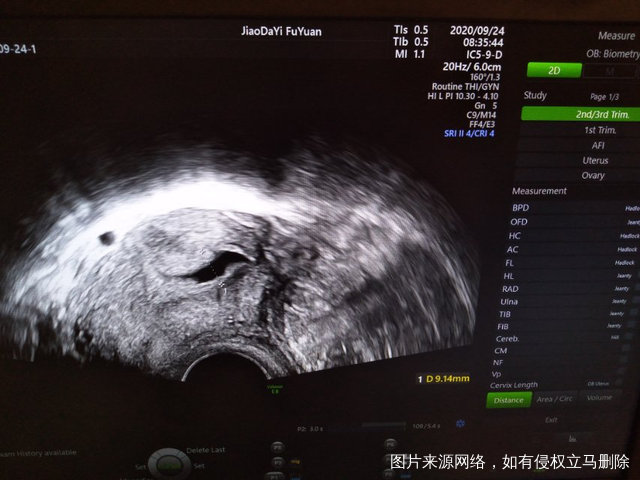

试管婴儿移植已经进周但有内膜分离的情况医生怀